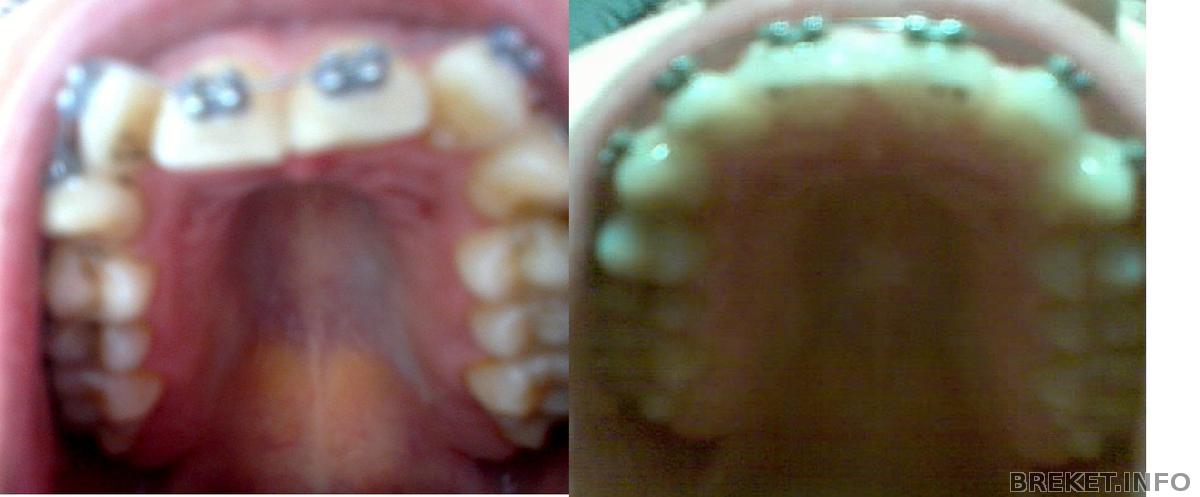

Вот фото (не очень хорошего качества) 1 и 5 месяц ношения БС.